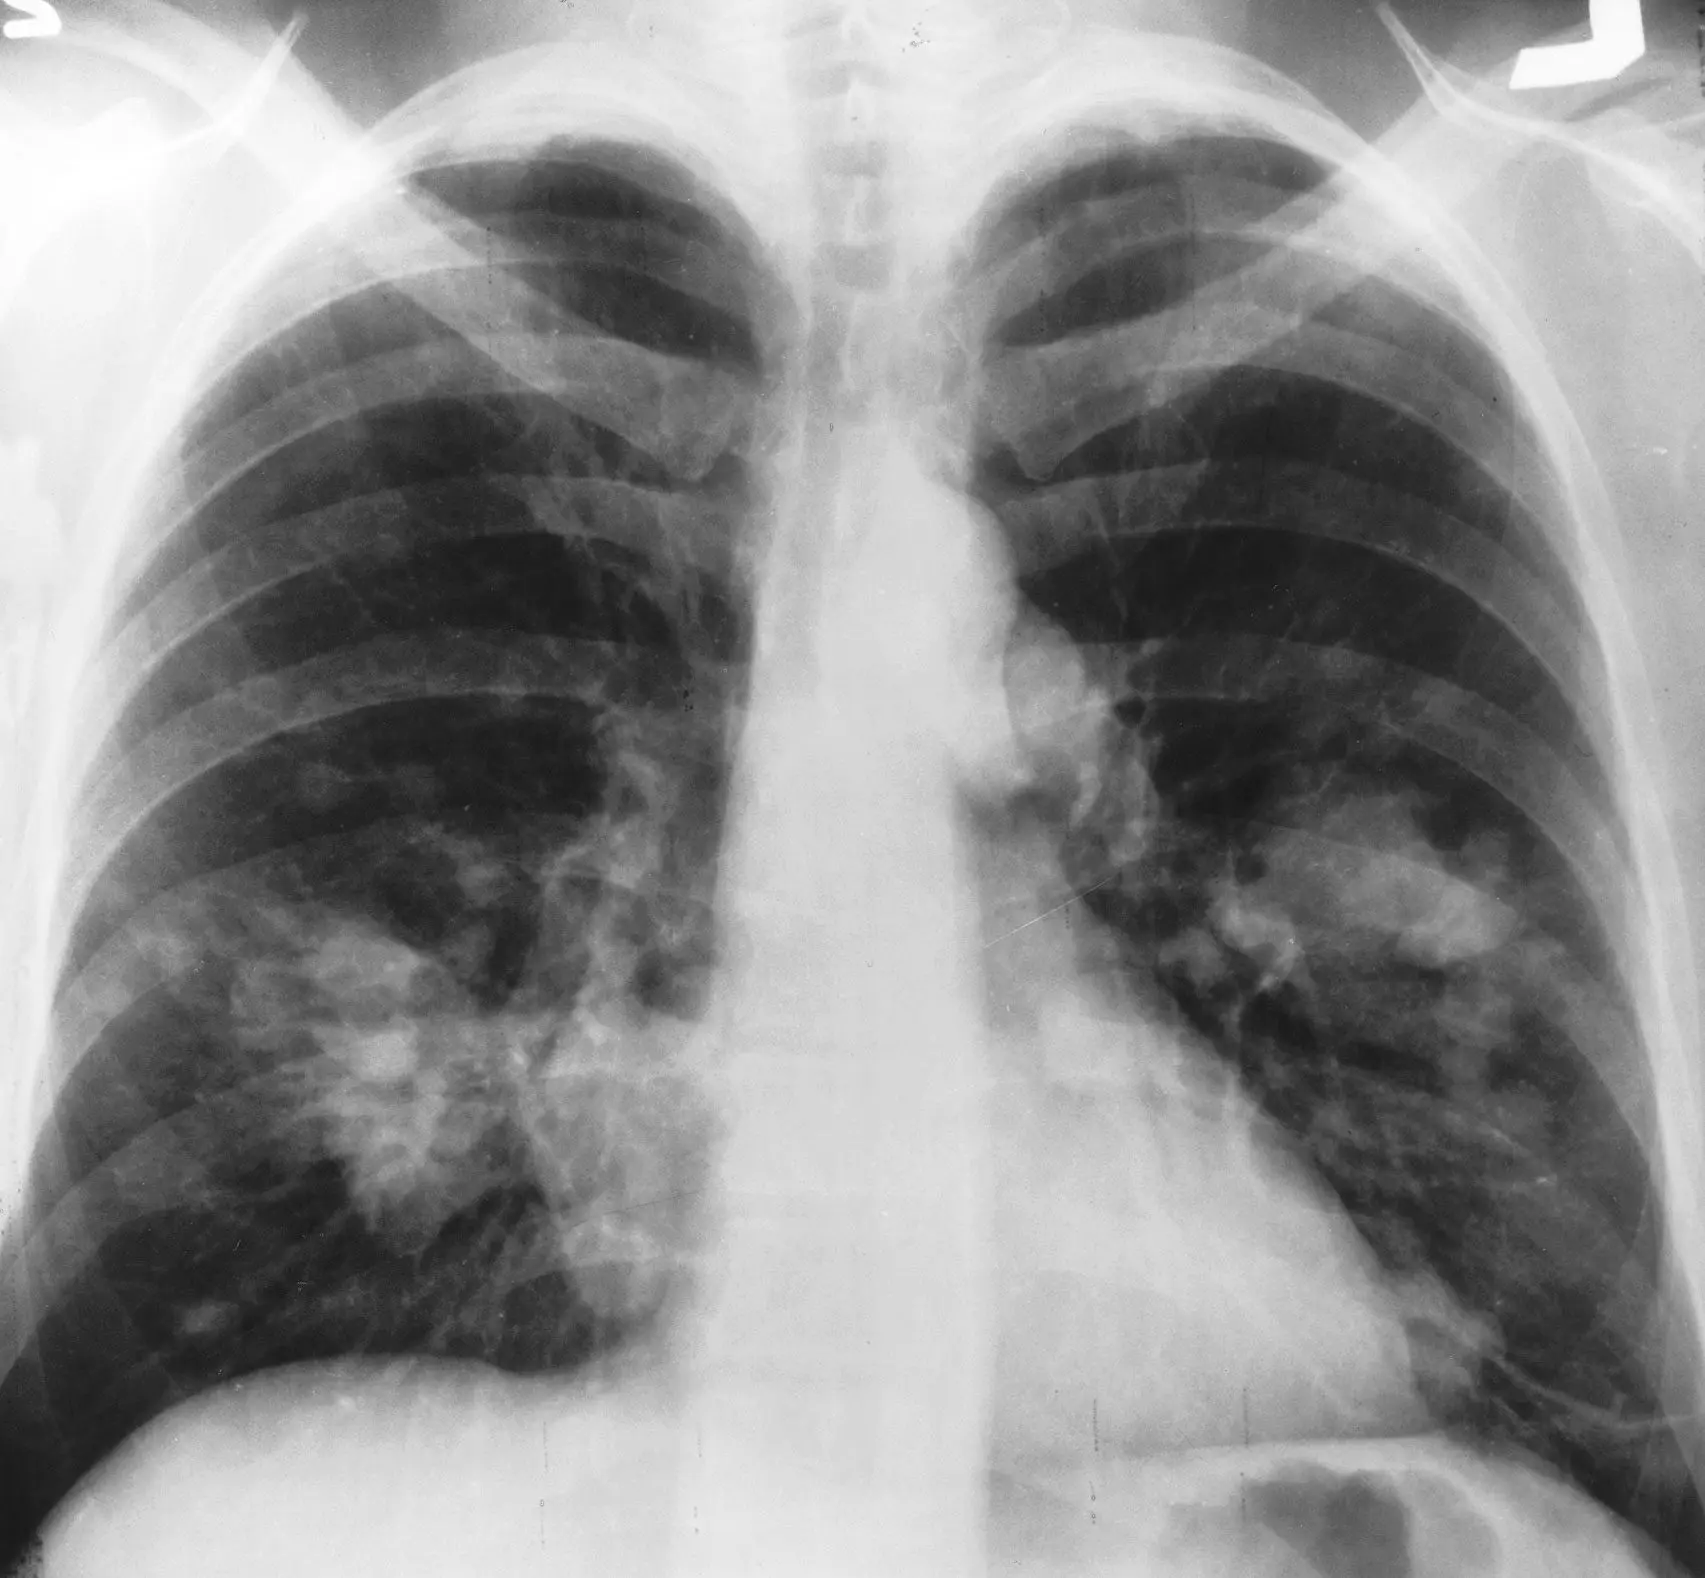

Lung cancer can be central and peripheral. The central type grows from the large bronchi, the peripheral kind – from the small ones.

Peripheral cancer is divided into the following types:

- nodular tumor;

- pneumonia-like cancer;

- carcinoma of the pulmonary apex.

Clinical signs manifest early only in central cancer. The leading symptom is cough, it is present in 90% of patients. Initially, the cough is dry, and it is associated with irritation of the receptor apparatus. Sputum appears after the tumor enlargement and bronchial obstruction.